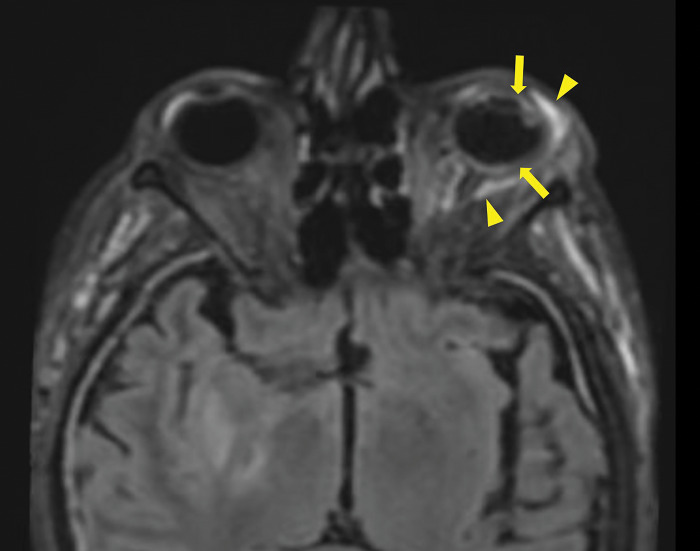

MRI Findings of Endogenous Endophthalmitis as a Complication of Pneumococcal Meningitis.

Teaching point: Endophthalmitis is an uncommon but severe complication of meningitis that can be visualized on MRI.